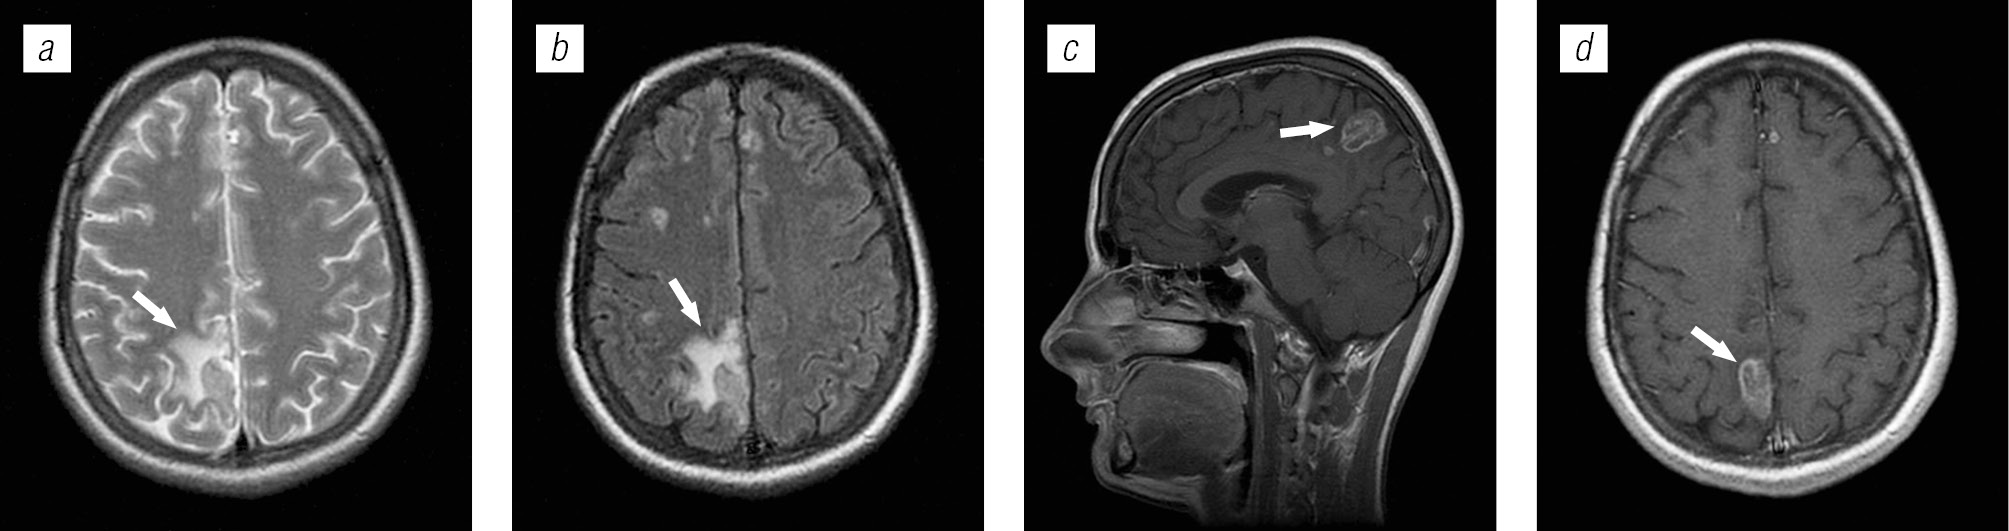

Материалы и методы исследования. В работе исследованы клинические и радиологические проявления поражения головного мозга у ВИЧ-инфицированных больных, поступающих в различные лечебные учреждения с диагнозом «ВИЧ-инфекция». Лучевое обследование головного мозга проводили взрослым ВИЧ-инфицированным пациентам (n = 410) при помощи магнитно-резонансной томографии с внутривенным контрастированием. Окончательный диагноз определяли с учетом клинических, лабораторных, радиологических исследований по Международной классификации болезней 10-го пересмотра в соответствии с отечественными требованиями формулирования коморбидного диагноза.

Заключение. Для правильной расшифровки природы поражения головного мозга необходимо использовать комплексные исследования, в том числе клинико-лабораторные и лучевые методы. Магнитно-резонансная томография с внутривенным контрастированием является методом выбора при обследовании головного мозга у ВИЧ-инфицированных пациентов.

Структура поражения головного мозга у ВИЧ-инфицированных больных имела различную природу: в 54,4 % случаев обнаружены признаки оппортунистических и вторичных заболеваний, в 24,9 % — признаки ВИЧ-энцефалопатии, в 13,2 % — признаки неспецифических изменений мелких сосудов головного мозга, указывающие на преждевременное старение или аномалию развития; в 7,56 % признаки вовлечения головного мозга в патологический процесс не выявлены.

Структура оппортунистических и вторичных заболеваний была представлена токсоплазмозом головного мозга (18,3 %), герпесвирусными поражениями (12,2 %), прогрессирующей мультифокальной лейкоэнцефалопатией (10,24 %), нейроинфекцией неуточненной этиологии (12,2 %), криптококкозом (4,39 %), туберкулезом (2,44 %), лимфомой головного мозга (2,44 %), МАК-инфекцией (0,24 %).